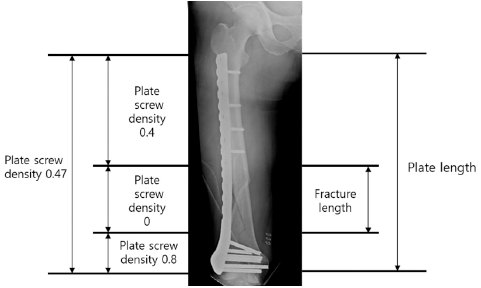

Fig. 3

Appropriate plate length and plate-screw density after minimally invasive plate osteosynthesis using a locking plate in osteoporotic distal femur fractures.